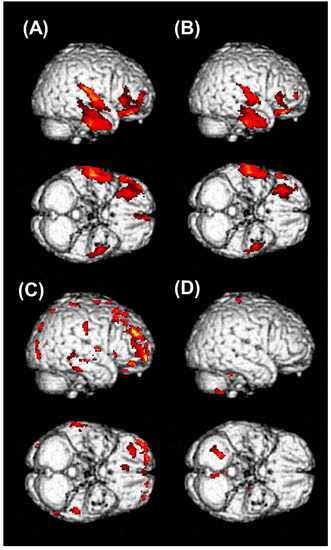

| 1 | Decreased metabolic activity in frontal and temporal lobes | Improved but remained | Improved but remained | 53 | 41 | 6 | 12 |

| 2 | Decreased metabolic activity in frontal and temporal lobes | Improved | Improved | 6 | 3 | No | 3 |